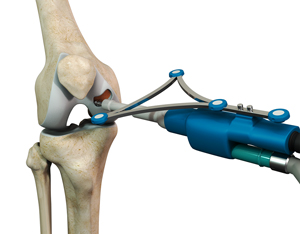

NAVIO

What is Smith & Nephew Navio Robotic TKR? Navio robotic TKR is a new surgical technique developed by Smith & Nephew which …